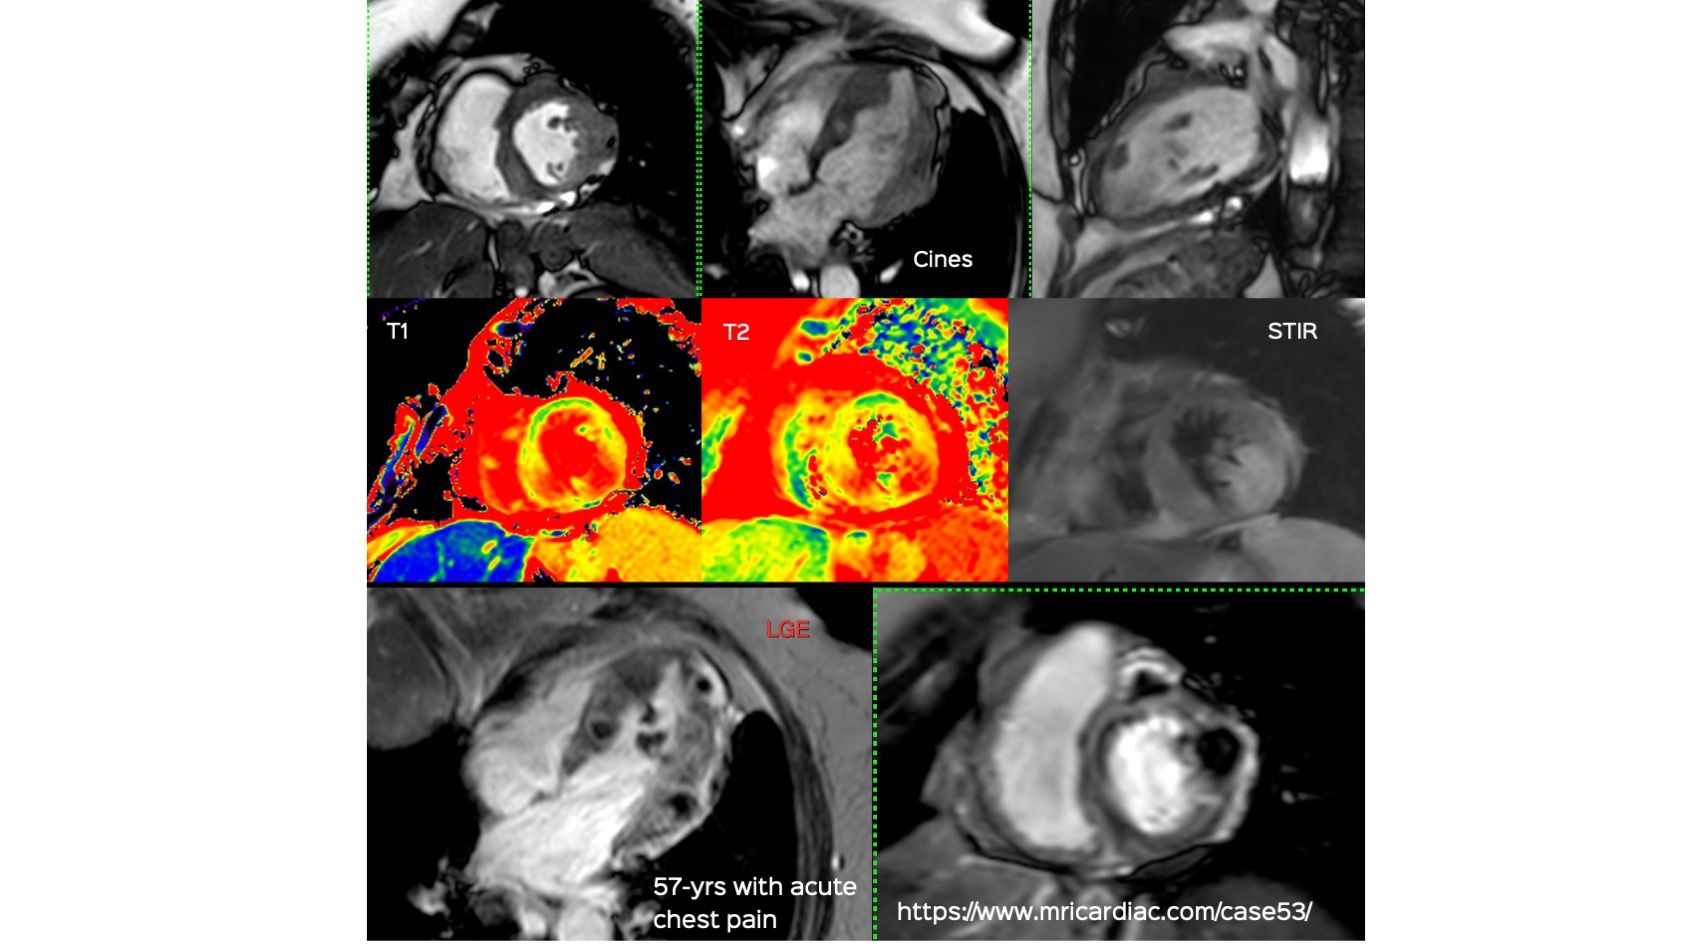

This 57-years old presented with acute chest pain. She was diagnosed to have a non-STEMI infarct. Coronary angiography and echo were done. Based on the echo findings, an MRI was done, which uncovered a myriad of findings. The video explains the rest. Do Subscribe to View - It’s Free